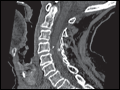

| Figure e44-37 Odontoid fracture Sagittal CT demonstrates disruption of the main reference cervical lines. 1: Anterior vertebral body line; 2: Posterior vertebral body line; 3: Spinolaminar line. | |

view large |